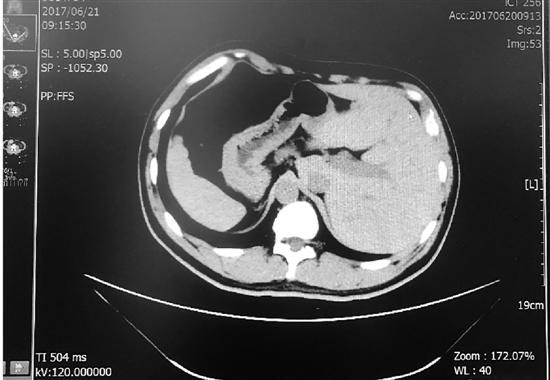

圖為影像片